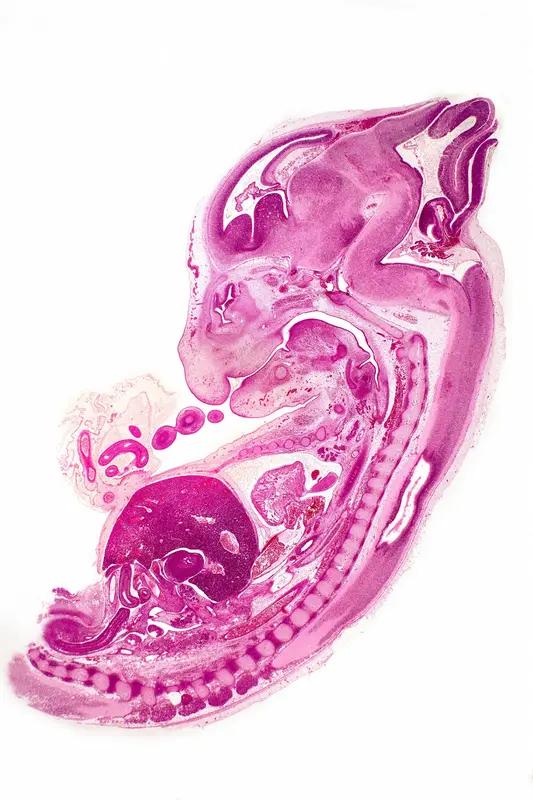

引起输卵管积液的原因是什么